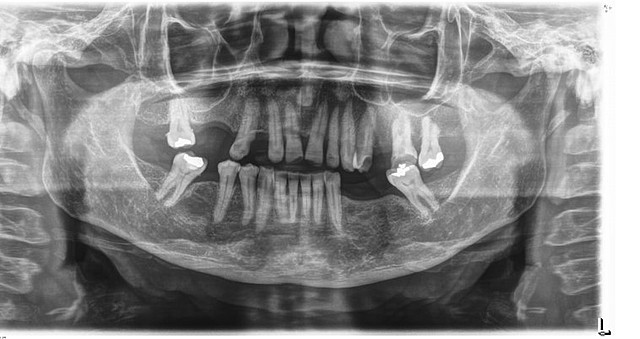

• Radiografías

Radiografías

Se observaron varias ausencias dentales y migración patológica.